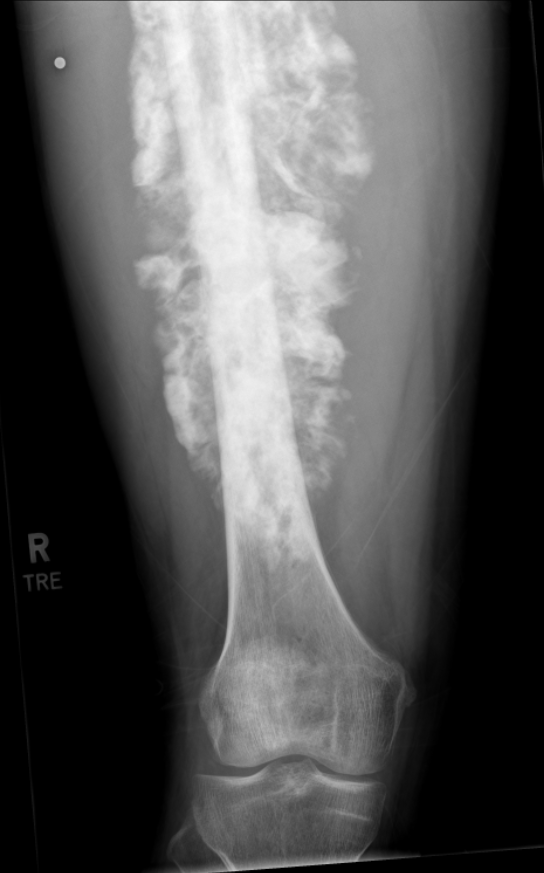

The preliminary x-rays showed visible cloudiness around my femur, an indicator of bone cancer, which prompted a frightening response by the doctors and I was referred to a team of Oncologists with the Utah Cancer Specialists. In the following two weeks I had an MRI, full-body PET scan, chest and abdomen CT scan, heart ECHO, and a bone biopsy. The bone biopsy came back positive for high-grade Osteosarcoma and in less than a week I had an IV port installed in my chest and was scheduled for chemotherapy.

Osteosarcoma has a very aggressive nature and can rapidly metastasize to the lungs. Thankfully all of my scans showed that the cancer was localized to my leg, which greatly increased my prognosis of having a positive outcome, however the cancer had already spread through 12 inches of my femur and the surrounding soft tissue. With my life literally on the line I had no time to spare and started my first round of chemotherapy on August 26th, 2025.

Osteosarcoma requires what is called the MAP chemotherapy regimen and is a combination of the drugs Methotrexate, Doxorubicin (The Red Devil), and Cisplatin administered over the course of a 35-day cycle. As I am writing this, I have just completed chemo cycle 2, will be having surgery after chemo cycle 3, and will need to complete 6 total cycles of chemotherapy. Clinically speaking, the chemo seems to be working as it has almost completely cut out the pain and swelling. My most recent MRI in preparation for surgery shows that the tumor itself is the same size, but my lungs are still clear! This means the chemotherapy might not necessarily be shrinking the tumor, but it has stopped the cancer in its tracks for now, which is relieving news.